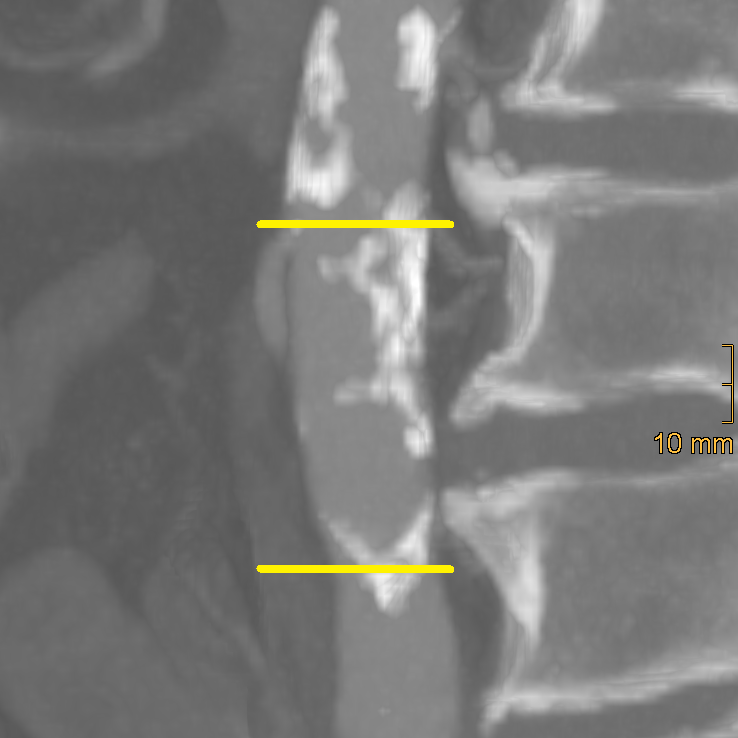

Aortic calcification was assessed using the method described by Reddy et al. [25], evaluating the segment between the origin of the inferior mesenteric artery and the aortic bifurcation. First, multiplanar reformations were generated to correct for aortic elongation. These were subsequently reviewed in sagittal orientation. To further enhance the visualisation of calcifications, 20 mm maximum intensity projections were created. Final image assessment was performed in a standard bone window (window width = 2500 HU; window level = 300 HU). Both the anterior and posterior walls were scored individually from 0 to 3 based on the longitudinal extent of calcification (0 = none, 1 = <33%, 2 = 33–66%, 3 = >66%). The total abdominal aortic calcification score (AACS) ranged from 0 to 6 and was classified as 0–2 = none to mild, 3–4 = moderate, 5–6 = severe. An example of AACS classification is provided in Figure 1.

Figure 1.

Axis-corrected sagittal reformation of the distal abdominal aorta. The yellow lines mark the origin of the inferior mesenteric artery and the aortic bifurcation. There is only punctual calcification at the anterior wall (=1 point), whereas more than two-thirds of the posterior wall show calcifications (=3 points). Accordingly, the AACS equals 4.